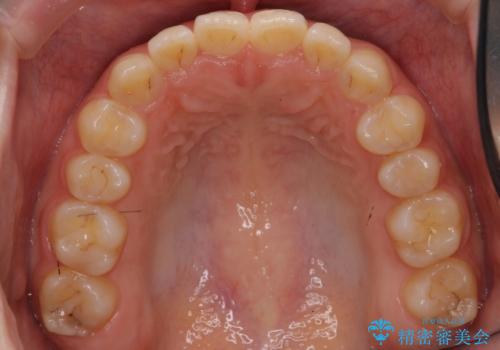

前歯のねじれ 乳歯を残して矯正治療

- 前歯のねじれを気にして来院。

左下に乳歯が残っていましたが、被せ物に穴が空いている状態でした。

乳歯は抜かずに保存的な治療を行いました。

上下の正中が1本分ずれていましたが、ちょうど1本分で目立たず、また、右下の歯が生まれつき少ないことを利用して、最小限の歯の移動にとどめました。